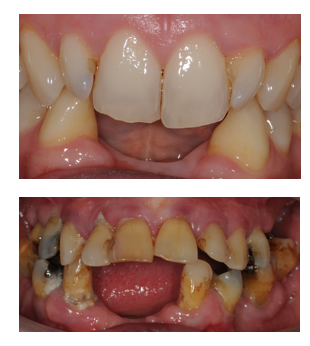

What are contraindications for conventional bridgework?

Unrestored abutments.

Poorly motivated patients.

Active caries or periodontitis.

Poor manual dexterity.

Large edentulous spaces.

Contact sports players.